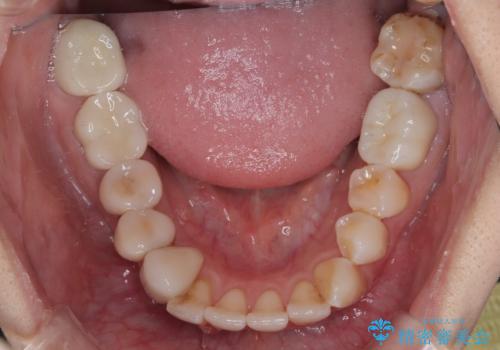

前歯をブリッジとするか否か、非常に悩まれていらっしゃいましたが、術前と比べてものが挟まる感覚がなくなったとのことで、大変満足されていました。

インプラントが必要となった奥歯は、インプラントが埋入できないほど隣の歯の根尖病変が非常に大きかったため、根管治療を行ったうえで半年ほど待ち、骨が再生したことを確認してからインプラントを埋入しました。期間は長くかかりましたが、大変良い仕上がりとなりました。